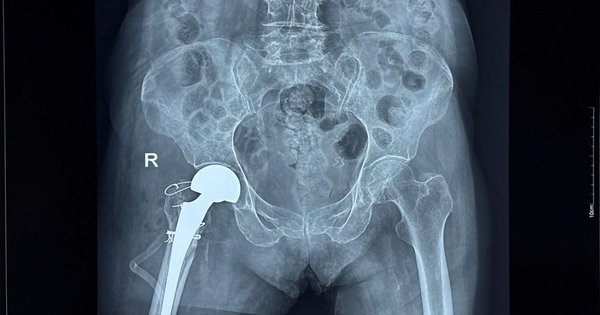

Thay khớp háng thành công cho cụ bà 100 tuổi

Cụ bà 100 tuổi bị tai nạn sinh hoạt tại nhà chấn thương nghiêm trọng đã được phẫu thuật thay khớp háng thành công tại Bệnh viện đa khoa Trà Vinh.